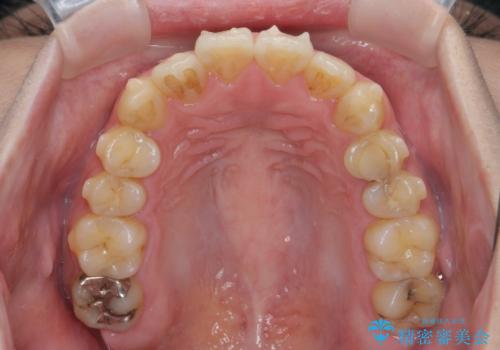

歯を抜かずに行う前歯の角度の改善

- 歯を抜かずに前歯の角度を改善したい、と矯正治療を希望され来院されました。

可及的に前歯部にIPR(歯間の削合)を行い、抜歯をせずマウスピース矯正システムインビザラインで歯の排列を行っていく治療計画としました。

治療の前後を比べると、がたつきや歯の角度が改善したことがしっかりと確認されました。